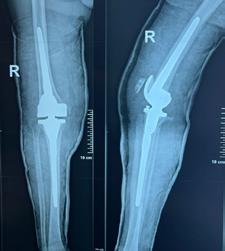

copul. Prezentarea unui caz complex rezolvat în Clinica Ortopedie -Traumatologie din cadrul SCJU Craiova al unui pacient ce a suferit un traumatism postoperator, cu ruptura ligamentului rotulian si complicarea septică a implantului, ce a necesitat revizia în doi timpi și refacerea mecanismului extensor folosind grefă sintetică.

În lucrarea de față vom prezenta cazul complex al unui pacient în vârsta de 84 de ani, ce a fost diagnosticat în primăvara acestui an cu Gonartroza bilaterala stadiul III, decompensata algic și functional pe dreapta, care în urma evaluării clinice, biologie și imagistice a urmat intervenția

de protezare a genunchiului, cu o evoluție postoperatorie favorabilă, fără complicații. În urma dispensarizării la domiciliu, la 3 săptămâni postoperator, pacientul suferă un traumatism prin cădere de la același nivel, prezentându-se în Serviciul de Urgență tardiv, după aproximativ 10 ore, cu o plagă dehiscentă pe fața anterioară a genunchiului, exteriorizându-se la piele ligamentul rotulian restant, dezinserat de la nivelul polului inferior rotulian. Intraoperator se practica debridare mecano-chirurgicala intensivă, cu îndepărtarea marginilor plăgii, ale țesuturilor necrozate, lavaj intens, abundent și sutura ligamentului rotulian (Fig 1; Fig 2).

Postoperator evoluția este nefavorabilă, cu modificarea markerilor biologici inflamatori (VSH, Fibrinogen, Proteina C-Reactiva ↑), prezența unei hidrartroze restante, pozitive la Staphylococcus aureus meticilino-rezistent (MRSA), ruptura suturii ligamentare, de unde și decizia unei revizii în doi-timpi, conform protocoalelor internaționale și inițializarea antibioticoterapiei țintite cu Linezolid 2mg/ ml, fl II/zi.

În prima etapă s-a îndepărtat proteza primară, s-a practicat debridarea mecano-chirurgicală a țesuturilor neviabile, rezecția ligamentului restant de la nivelul inserției sale tibiale, alezarea canalelor fe-

Prof. Univ. Dr. Dan Nelu Anușca

muro-tibiale, aplicarea perlelor de Stimulan atât in canalele osoase cât și în camera genunchiului, si montarea unui spacer femuro-tibial (Fig 3).

În a doua etapă, după parcurgerea curei antibiotice, se practică revizia cu implantele finale, folosind proteza de revizie de tip balama, cu stem femural și tibial lung, cu protecția oferită de perlele de Stimulan impregnate cu Vancomicină și Linezolid.

Particularitatea cazului o oferă tipul de tehnică chirurgicală folosită în refacerea ligamentului rotulian prin utilizarea unei grefe sintetice, de tipul Marlex mesh. (3) Din experiența noastră folosind multiple tipuri de grefe pentru reconstrucția ligamentului rotulian, rezultatele în timp s-au dovedit ineficiente (evaluarea la 1-3 ani postoperator indică resorbția cu dispariția ligamentului rotulian în întregime în mediu aseptic după folosirea grefei din Banca Națională de Țesut, fiind utilizată atât grefă cu pastilă osoasă calcaeană și tendon Achillean, cât și aparat extensor

întreg – dar osteointegrarea osoasă la nivelul TTA fiind completă), motiv pentru care am decis utilizarea unui substitut alloplastic- meșă (plasă) de polipropilenă 30x30cm care a fost preparată astfel: bucata de material a fost pliat în 8 straturi, având o l=3cm și o L=30 cm, fiind suturată cu fir neresorbabil pe lateralele sale, urmând a fi cimentată in canalul tibial odată cu componenta protetică tibială. După stabilirea indicelui Insall-Salvati corect, s-a folosit o langetă musculară din dreptul femural după tehnica Ducroquet care a acoperit noul ligament sintetic, oferind protecție si bază nutritivă și a fost stabilizat cu ajutorul a 2 ancore cu fire nerserobabile (Fig 4+5+6). Postoperator pacientul este imobilizat în aparat gipsat femuro-gambier pentru 6 săptămâni, mărind treptat gradul de flexie.